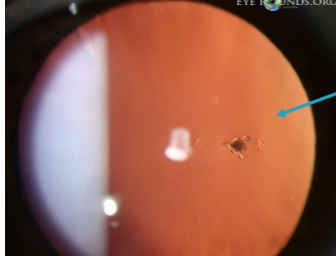

Mittendorf’s dot

remnant of tunica vasculosa lentis

remnant of hyaloid artery on posterior capsule

typically inferior-nasal

may have a tail

Mittendorf dot

Mittendorf dot & tail